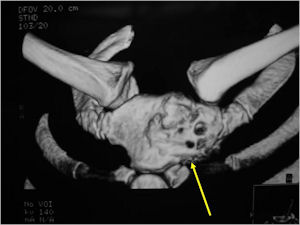

- Geographic, circumscribed lesion usually around 5cm in size.

- There may be expansion of bone, cortical thinning and cortical breakthrough. A soft tissue mass may accompany this lesion but the soft tissue component is usually contained by the periosteum.

- The periosteum remains intact around the soft tissue component. Might need a CT scan to detect the subtle calcification (Egg Shell Rim of Calcification) associated with an intact periosteal reaction

- The lesion may be entirely radiolucent but usually shows some degree of mineralization. Mineralization may appear stippled like cartilage but do not see chondroid pathologically. Mineralization is sometimes better detected on a CT scan rather than an x-ray.

- Arise from the Diaphysis (75%) more commonly than Metaphyseal (25%)

- 4 cm to 6 cm in size